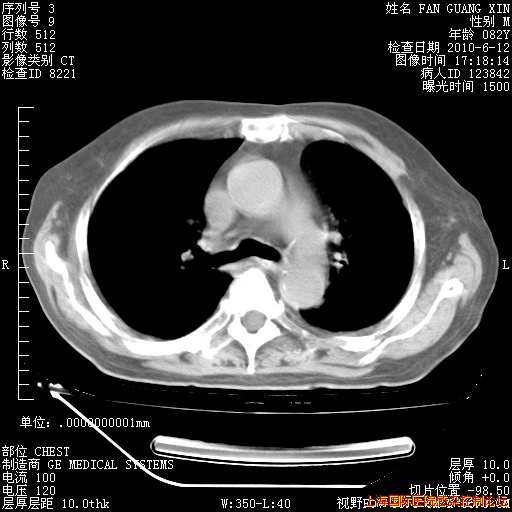

6月12日纵膈窗

补发6月12日肺部CT肺窗

6月12日肺窗